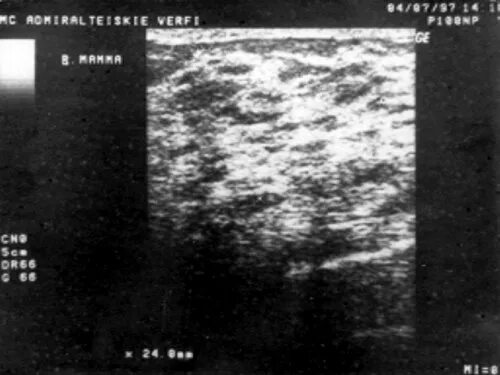

Диффузные изменения фиброзного характера